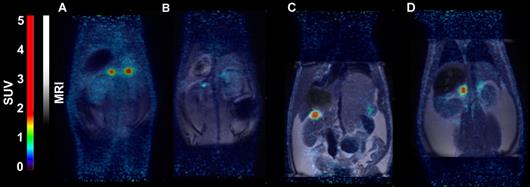

Figure 8

Representative coronal PET (A) and PET/MRI fusion (B, C, D) SUV images in rat 30 min post injection of [18F]CETO (A, B) and [18F]FETO (C, D), without (A, C) and with (B, D) blockage with 1μmol/kg metomidate.

In rats, [18F]CETO uptake, by contrast, was concentrated mainly in the adrenal glands (Fig. 8A-B). Peak adrenal uptake was determined to 120 min p.i. in rats. The uptake of [18F]FETO in rats was also concentrated mainly in the adrenal glands. However, we were unable to block the uptake with metomidate (Fig. 8C-D). For both rats and NHPs, the elimination of [18F]CETO was mainly renal.